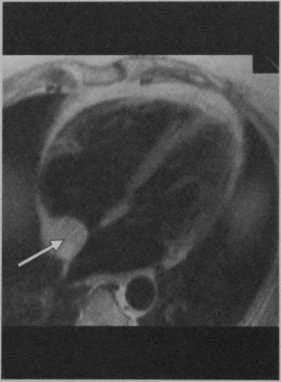

Тот же пациент.Т1 -взвешенная последовательность TSE с темной кровью на четырехкамерном срезе демонстрирует гиперинтенсивное образование с растворением жировой ткани, граничащее с задней частью межпредсердной перегородки (стрелка).